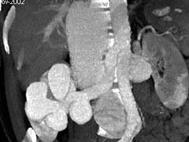

男,18岁,请根据所示图像,选择最可能诊断 ( )A、右侧肾癌B、右肾动静脉畸形C、右肾出血D、右肾囊肿E、右肾积水

问题 男,18岁,请根据所示图像,选择最可能诊断 ( )

选项 A、右侧肾癌 B、右肾动静脉畸形 C、右肾出血 D、右肾囊肿 E、右肾积水

答案 B